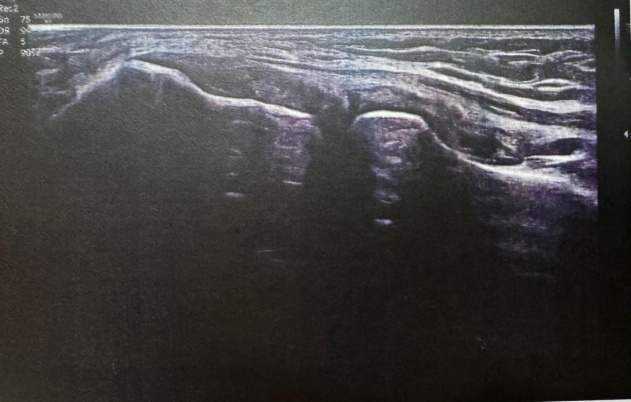

Fig. 1 Fig. 2

Fig. 3 Fig. 4

Fig. 1-6: Ultrasound image report

Ultrasonography of right elbow joint

No significant free fluid seen in elbow joint region.

The visualized cortex of distal humerus and proximal radius appears normal and show no breach at present scan.

Visualized muscles and tendons appear normal and show no tear at present scan.

No evidence of any inflammatory changes seen in elbow joint region. There is a tiny well defined hypoechoic area approx 1.25 cms from the skin seen in proximal ECRB (extensor carpi radialis brevis).